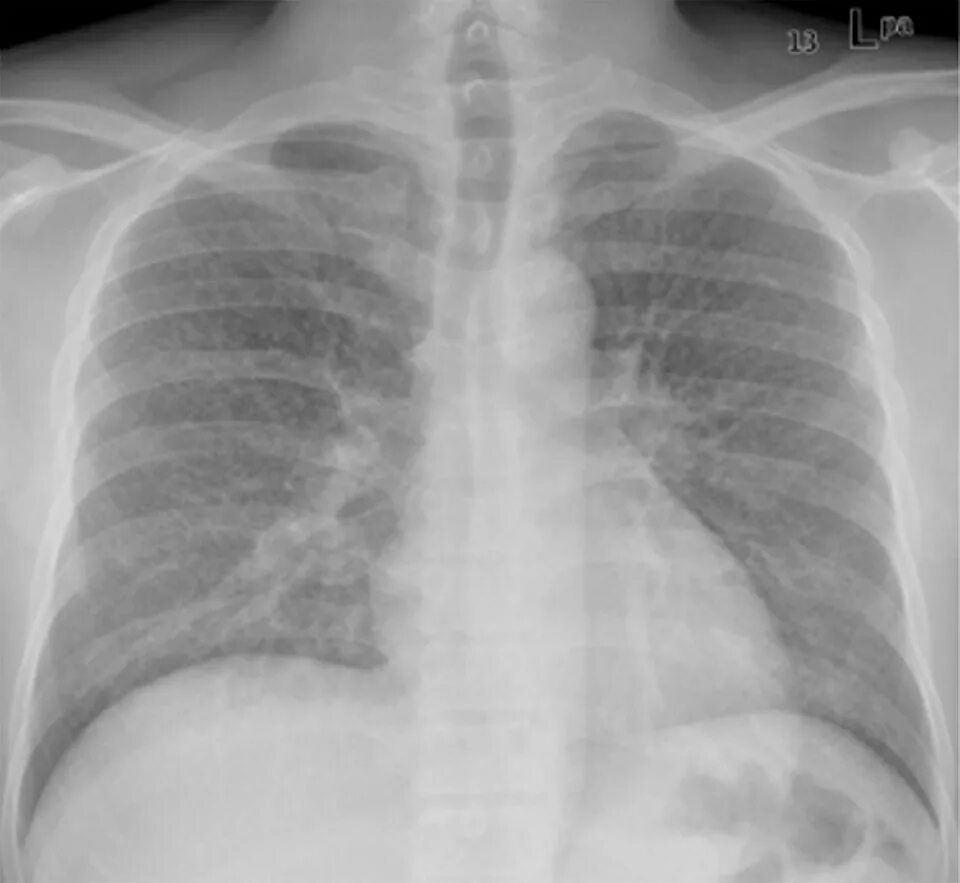

Единичные метастазы в легких